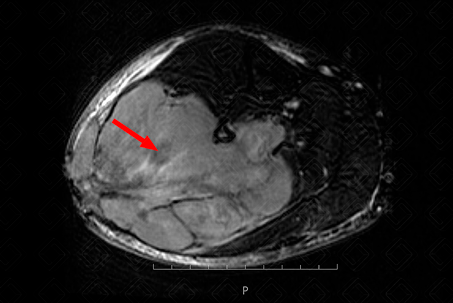

Texto alternativo para a imagem Figura 2. Créditos: Athena Hub/Medical Harbour

Descrição da figura 2: Ressonância magnética de membros inferiores, T1 pré e pós-contraste evidenciando discreto realce da lesão na sequência T1 pós-contraste (seta vermelha).